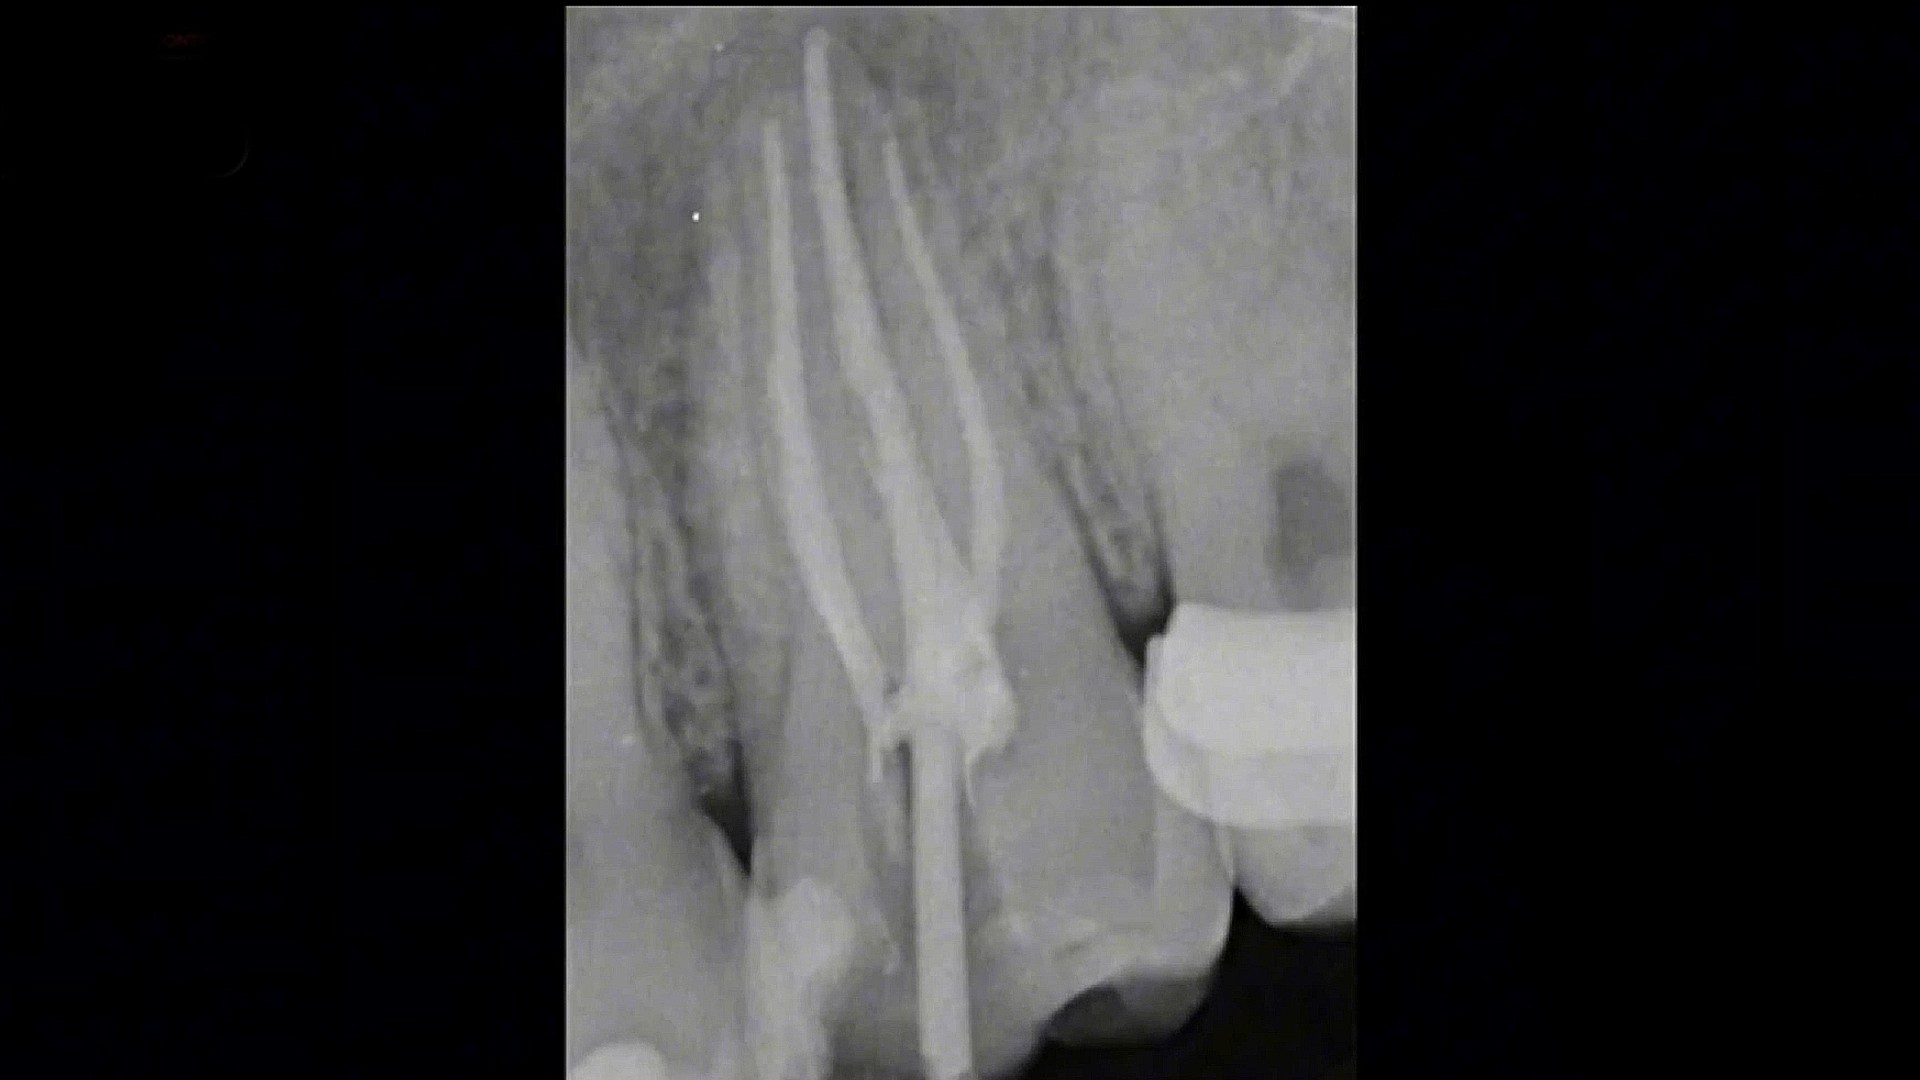

HOW TO MANAGE LARGE PERIAPICAL LESION WITH NON-SURGICAL ENDODONTIC TREATMENT